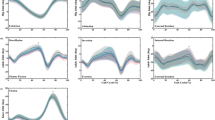

There was no significant change in flexibility or energy absorption in the normal group (P = 0.081) from 1 to 10,000 cycles; however, these values decreased significantly with time in the obese and insole groups (P < 0.001; Fig. 6). Meanwhile, the difference between 1 and 10,000 cycles in flexibility and energy absorption in the insole group were significantly lower than in the obese group (P = 0.026; Fig. 7).

Time-dependent change in flexibility and energy absorption. Time-dependent changes in flexibility (a) and energy absorption (b) in the normal, obese, and insole groups. Coordinate points represent mean change; bars represent 95% confidence intervals. Flexibility and energy absorption decrease significantly over time in the obese and insole groups (* P < 0.001 for both), but not in the normal group (P = 0.081)